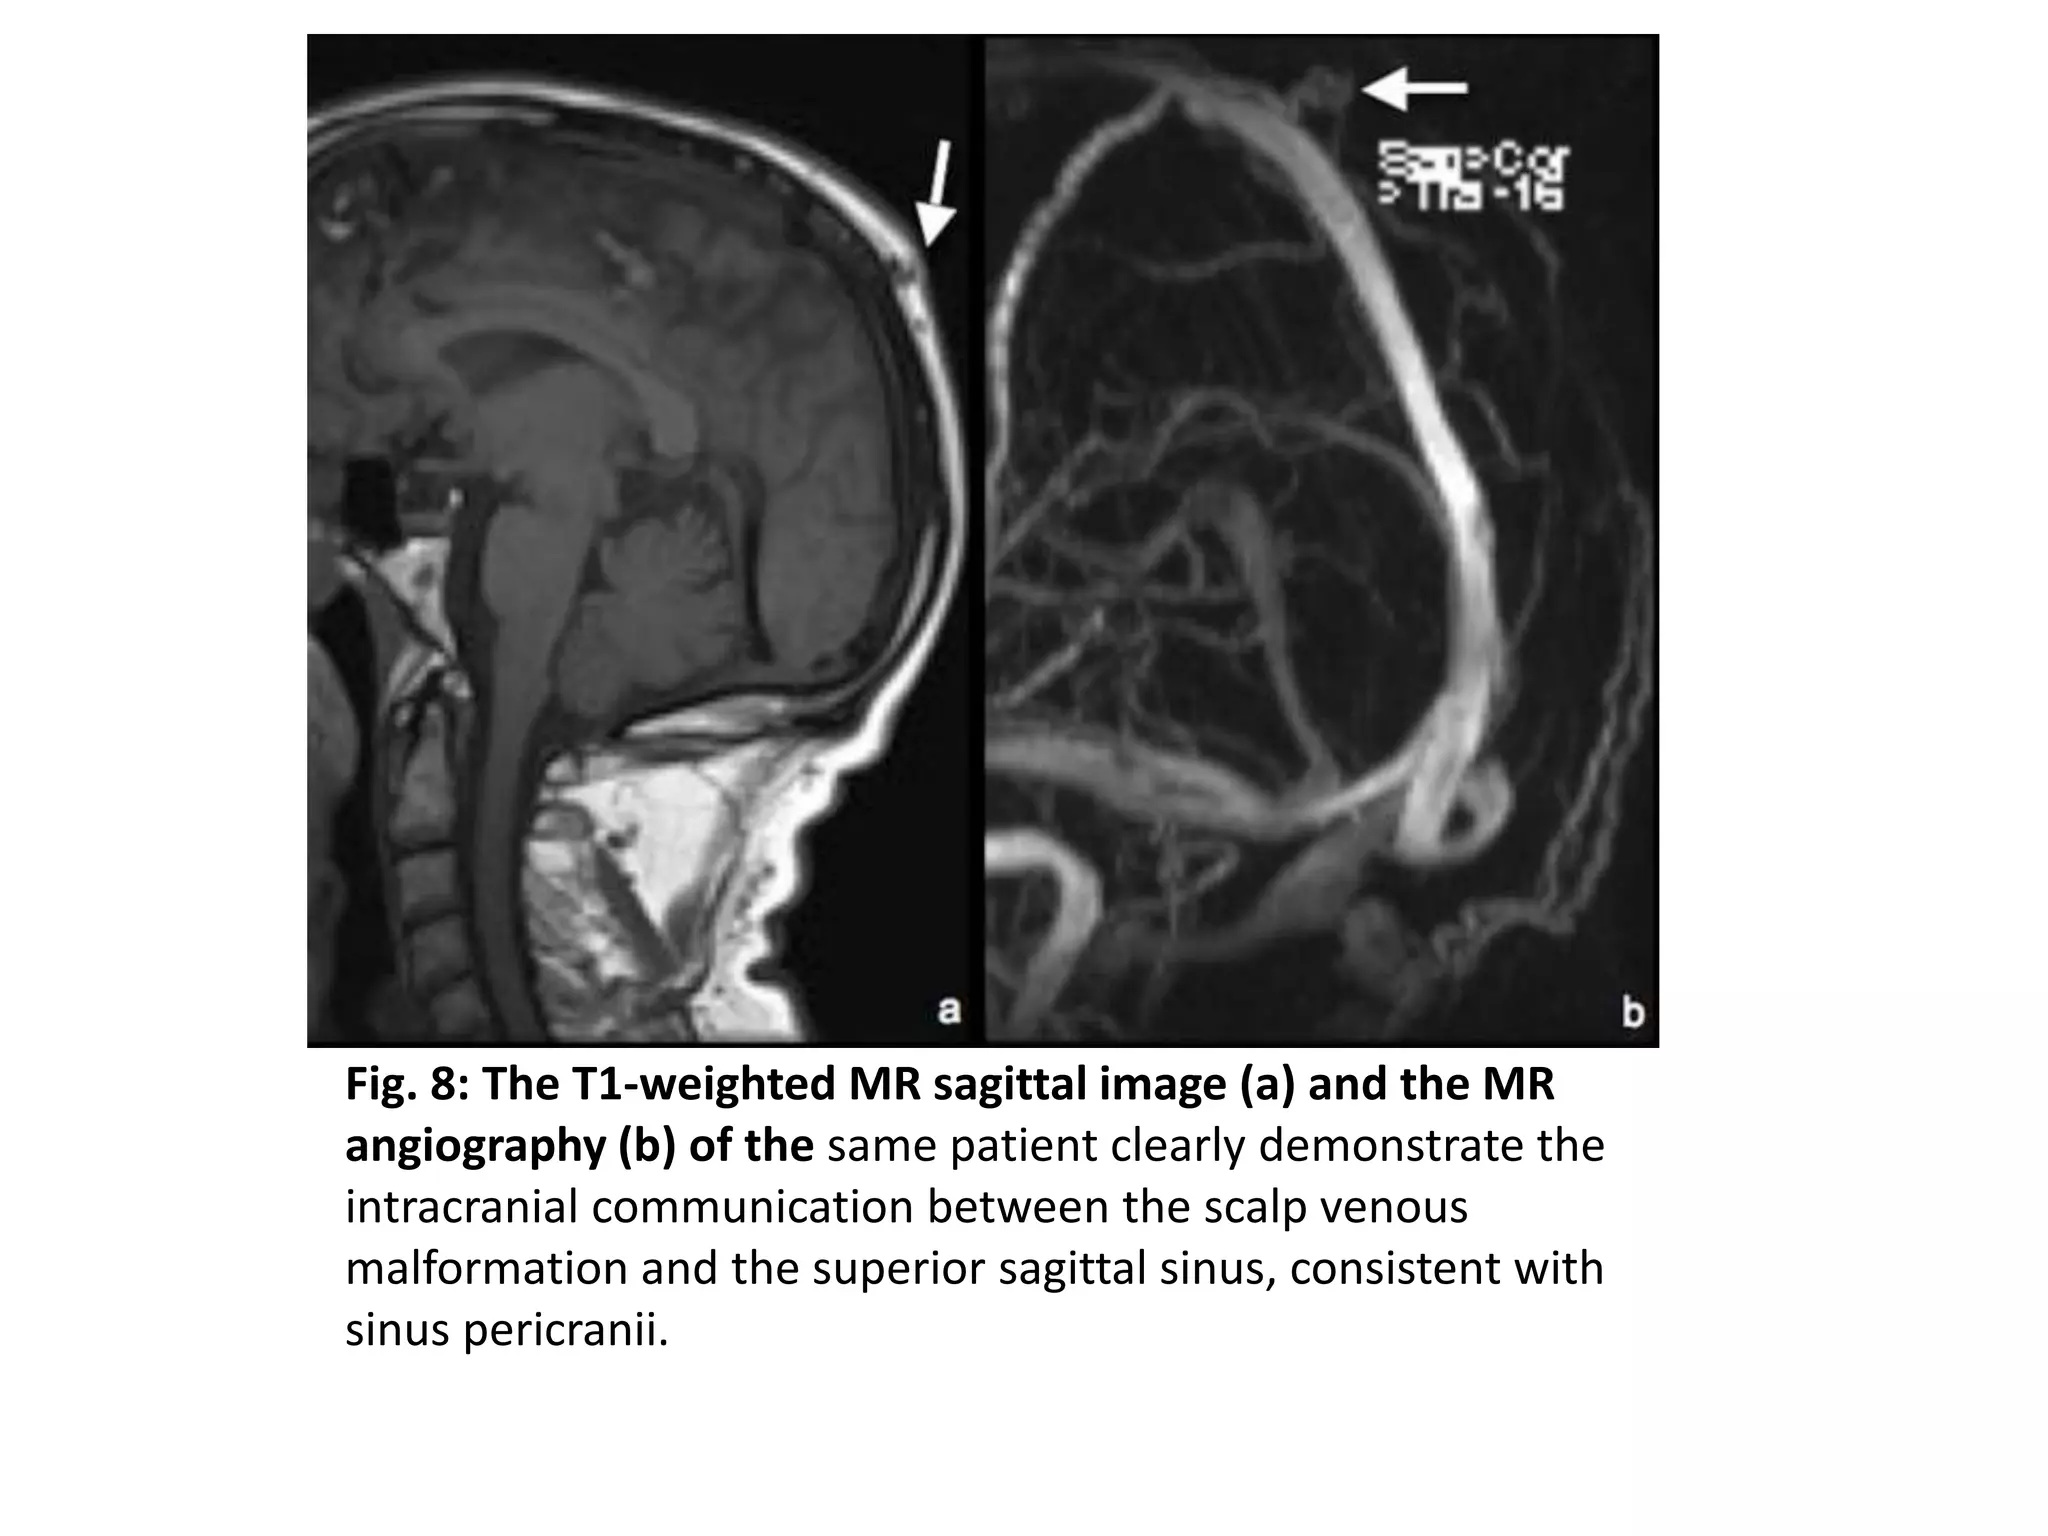

Fig. 8: The T1-weighted MR sagittal image (a) and the MR

angiography (b) of the same patient clearly demonstrate the

intracranial communication between the scalp venous

malformation and the superior sagittal sinus, consistent with

sinus pericranii.

Fig. 8: TheT1-weighted MR sagittal image (a) and the MR angiography (b) of the same patient clearly demonstrate the intracranial communication between the scalp venous malformation and the superior sagittal sinus, consistent with sinus pericranii.